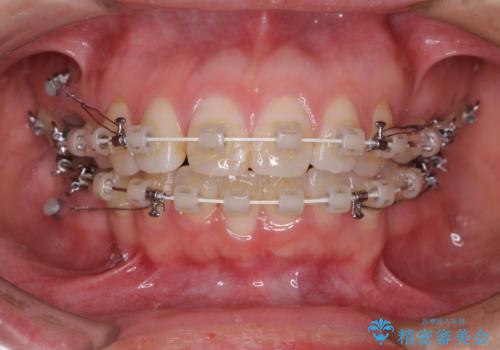

- 矯正装置

- 審美装置

- 2年10ヶ月

- 10-30回